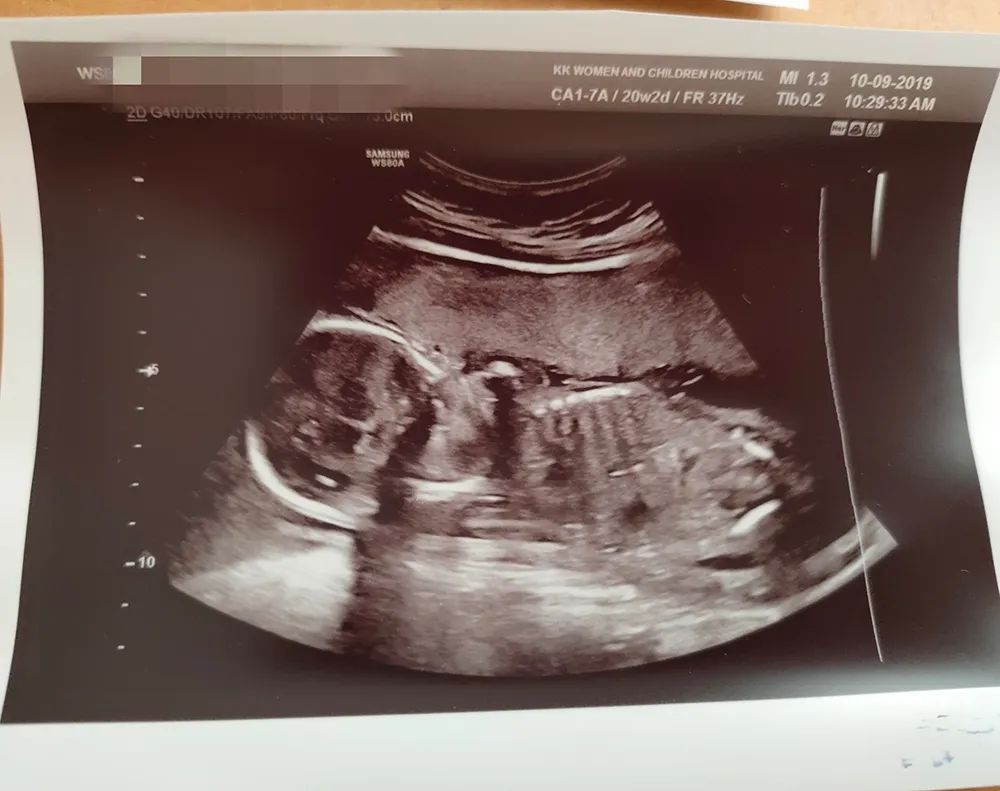

第三次产检&大排畸 血糖检测第三次的产检在孕20-23周期间,届时会通过B超进行大排畸检查,以确定宝宝的发育状况,筛查宝宝表面畸形,这时也会清楚地看到宝宝的性别。

很多孕妈听说国内的大排畸检查需要憋尿,其实根本不需要,如果膀胱中存有过多的尿液,不容易看到胎宝宝的情况哦。大排畸的B超检查通常会持续15-30分钟,虽然没有国内的四维彩超,但是看到宝宝的各个器官、四肢等等,还是超兴奋的。